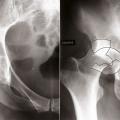

Les fractures du massif trochantérien peuvent être classées en fonction de la position du trait de fracture. Les fractures cervico-­trochantériennes se rapprochent des fractures basicervicales. Les fractures per-trochantériennes, plus ou moins complexes, sont situées à l’intérieur du massif trochantérien. Les fractures trochantéro-diaphysaires concernent le massif trochantérien et la partie haute de la diaphyse. Les fractures sous-trochantériennes sont situées sous le massif trochantérien et sont à la limite entre les fractures de l’extrémité supérieure du fémur et les fractures diaphysaires. Il existe d’autres classifications (Ender, AO, etc.). Ce qui compte avant tout est d’apprécier le caractère stable ou instable de la fracture (fig. 10). Cette stabilité dépend de la comminution de la fracture et du détachement du petit trochanter. Il existe parfois des fractures localisées au grand trochanter dont il faut apprécier le déplacement lié à l’insertion du moyen et du petit fessier.